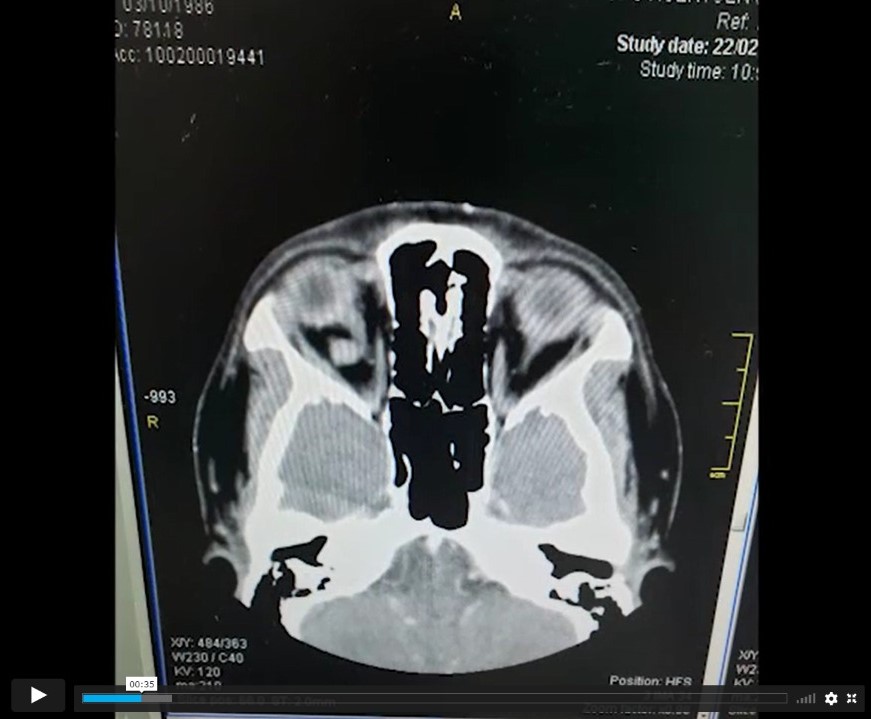

Tac se visualizan dos lesiones intraorbitarias derechas, intraconales, solidas, bien definidas, retrooculares, que contacta (la más interna) el nervio óptico y provoca una rotación externa del globo ocular.

Case Description: Pte. woman, 30 years who debuts with right proptosis, retrocular pain, diplopia, normal visual acuity.  Tac two right, intracontal, solid, well-defined, retroocular intraorbital lesions are displayed that contacts (the innermost) the optic nerve and causes an external rotation of the eyeball.

Los autores presentan un video titulado “ANGIOMATOSIS CAVERNOSA INTRAORBITARIA”. La presentación es clara y con buena locución, iniciando con el cuadro clínico, una secuencia de imágenes de TAC sin y con contraste seguido de RMN que evidencian 2 cavernomas intraorbitarios. Luego da comienzo al acto operatorio en donde se notan 2 tipos de cámaras: una manual HD a mano alzada y la otra la del microscopio con menor calidad que un HD que hace que la cirugía se luzca menos. Cabe destacar la claridad en la secuencia quirúrgica de la orbitotomía lateral, la explicación de la anatomía intraorbitaria y los tips para una correcta disección y resección de los 2 hemangiomas cavernosos; por último, la reconstrucción de la pared lateral de la órbita. El video cierra con el examen de la motilidad ocular al día siguiente de la cirugía.